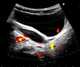

Dilated bladder

Urinary retention is an inability to completely empty the bladder. Onset can be sudden or gradual. [Source: Wikipedia ]